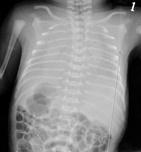

新生兒呼吸窘迫綜合征治療

• 新生兒呼吸窘迫綜合征

628健康網為您分享有關新生兒呼吸窘迫綜合征的癥狀,新生兒呼吸窘迫綜合征的治療方法,新生兒呼吸窘迫綜合征的預防知識...